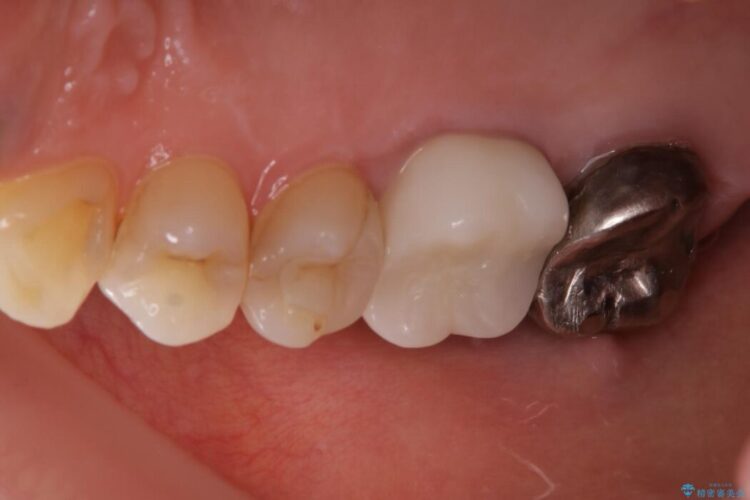

最終的にセラミッククラウンによる補綴治療を行いました。

適合の悪い補綴物は二次的な虫歯発生のリスクが高まります。

自費診療で用いられる材料は保険適応の材料に比べて、より精密で適合の良い被せ物作ることができるため、長期的な虫歯のリスクを大幅に減らすことが可能になります。